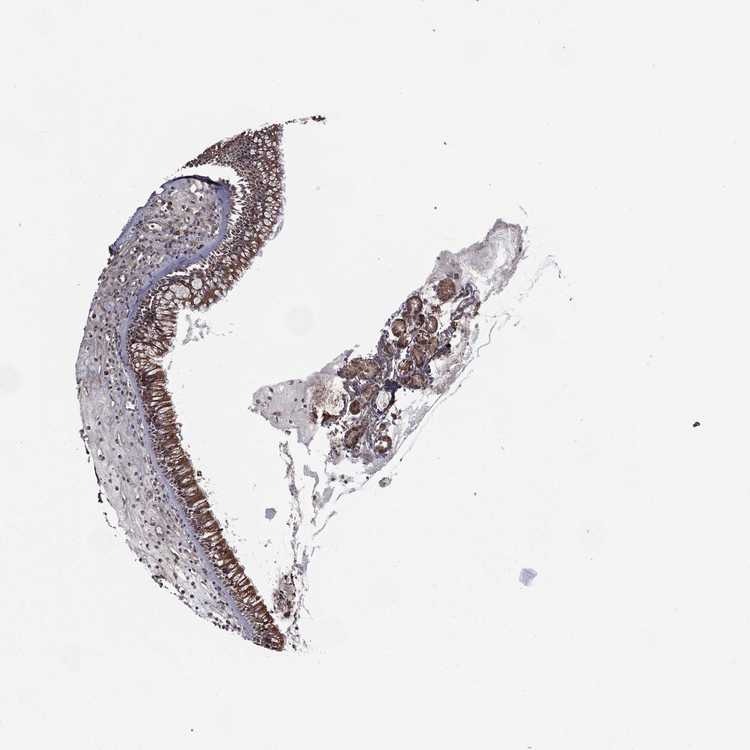

TISSUE PRIMARY DATA NASOPHARYNX Show tissue menu

NASOPHARYNX - Antibody stainingi

Antibody staining in the annotated cell types in the current human tissue is reported as not detected, low, medium, or high, based on conventional immunohistochemistry profiling in selected tissues. This score is based on the combination of the staining intensity and fraction of stained cells.

Each image is clickable and will lead to virtual microscopy that enables deeper exploration of all samples and also displays staining intensity scores, fraction scores and subcellular localization as well as patient and tissue information for each sample.

Antibody HPA058824

Respiratory epithelial cells Medium